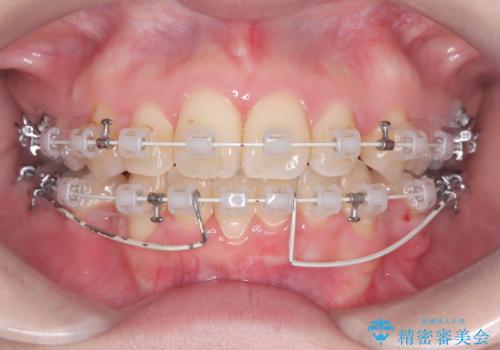

- 「歯のデコボコ、八重歯、口ボコが気になる」を主訴に来院された患者様です。

上下左右4番(4本)の歯を抜歯しワイヤー矯正で治療を行いました。

計4本の抜歯を行い、歯のデコボコと口元がすっきりし、大変ご満足していただけました。